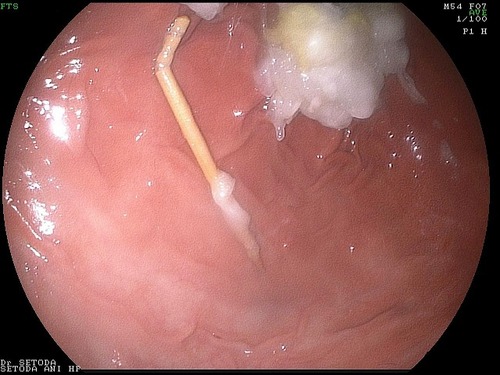

胃の中からつまようじを取り出す際に、胃や食道に傷をつけないように取り出すために、この折れ曲がった部分を持って、取り出すことにしました。

MAE00007.jpg